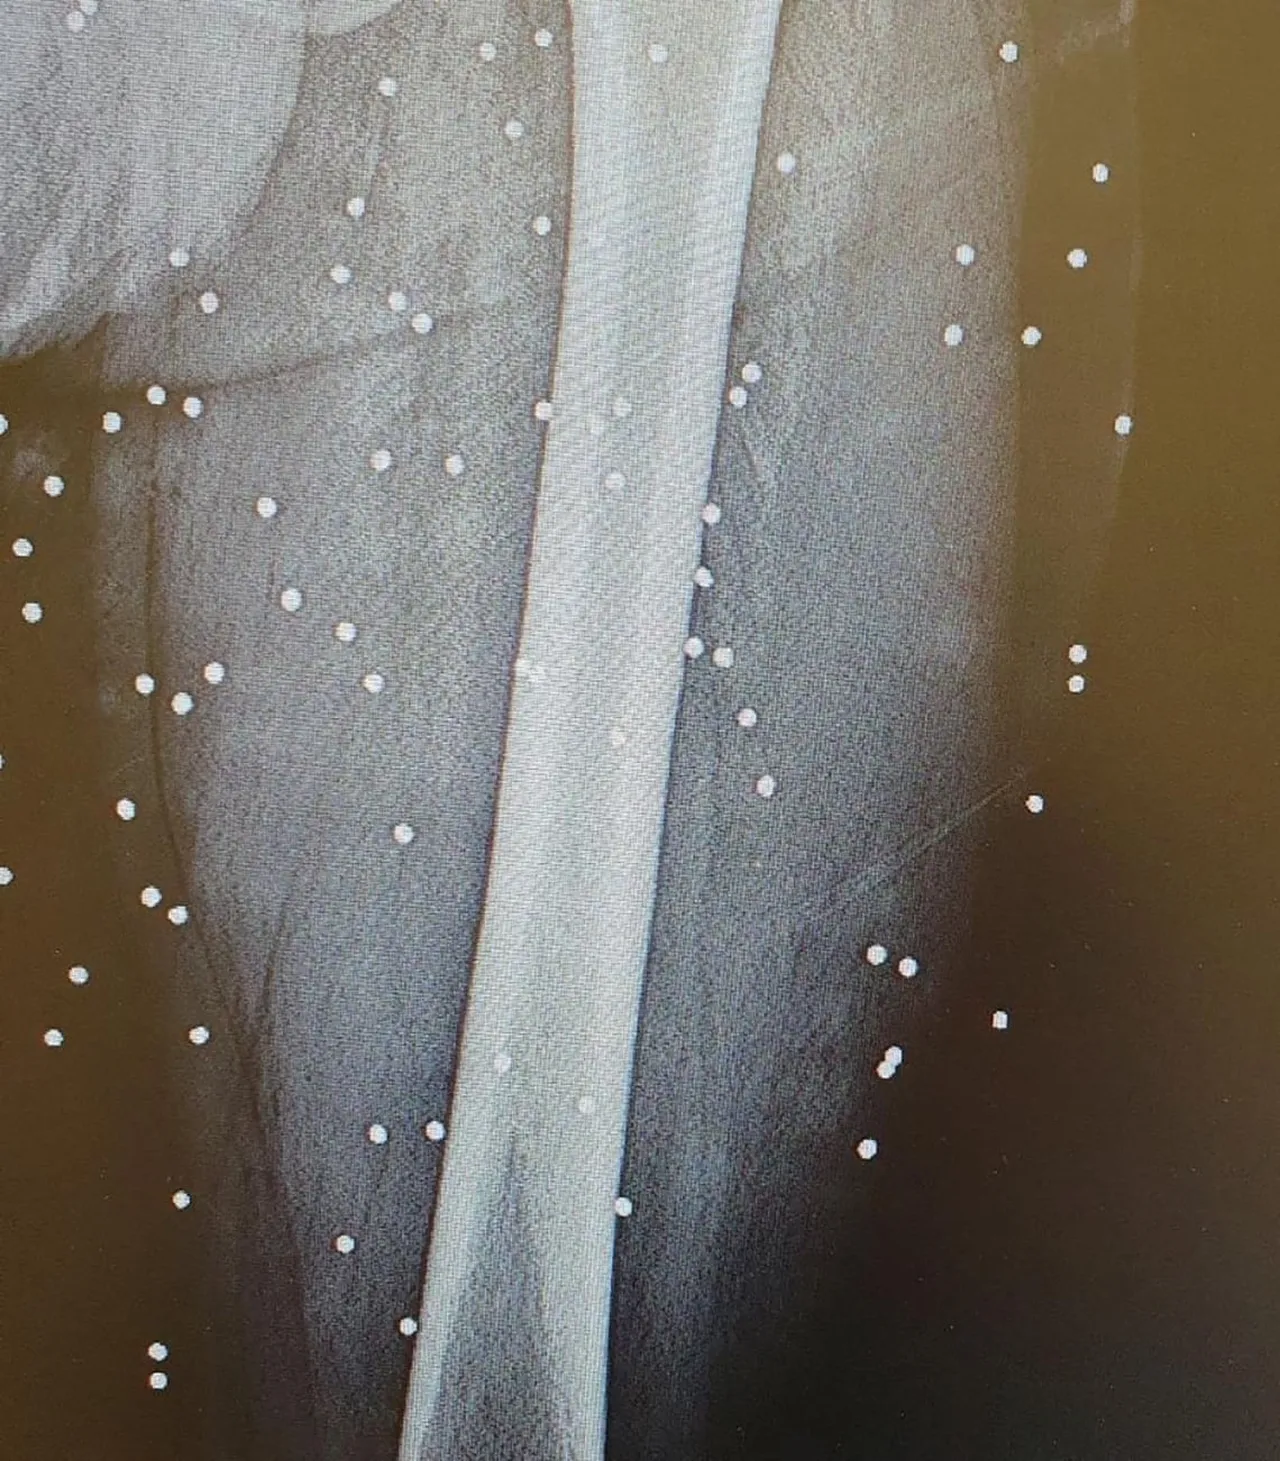

İnternet ve mobil iletişimin tamamen kesildiği 8 Ocak gecesi, hastaneler dakikalar içinde "kitlesel zayiat alanı"na dönüştü. Cerrah, başlangıçta saçma yaralarıyla gelen hastaların yerini, kısa süre sonra vücutlarının bir yanından girip diğer yanından çıkan gerçek mermilerle vurulmuş yaralıların aldığını anlattı.

Özellikle gövde yaralanmalarıyla ilgilenen ve çok sayıda mermi çıkardığını anlatan cerrah, "Uyarı atışı değildi. Bunlar onları öldürmek için kullanılan gerçek mermilerdi" ifadelerini kullandı.